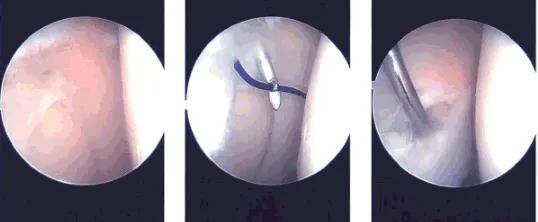

Intraoperative images

Examination of the lateral tibiofemoral compartment showed tear in the anterior horn as well as partial tear in the anterior root. The tear in the anterior horn was in the red-white zone and it was decided to repair it. Debridement of the anterior root of the lateral meniscus was performed.

The tear was prepped with the use of meniscal rasp and shaver. Outside-in repair was planned. Meniscal mender was opened and the straight needle was passed percutaneously laterally through the meniscus tear. The probe needle was advanced at the side of the straight needle through the tear.

Once it was in, the snare was passed out of the probe needle and PDS suture was passed through the straight needle The PDS suture was retrieved. A skin incision was given connecting the two sutures.

The PDS suture was replaced by #2-0 FiberWire. The repair was checked arthroscopically and found to be in a satisfactory position. The suture was knotted on the outside.

The final picture was taken and saved. The knee was thoroughly irrigated. To perform microfracture chondroplasty in the intercondylar notch to release the marrow into the knee to allow a good healing environment. Knee was drained completely.